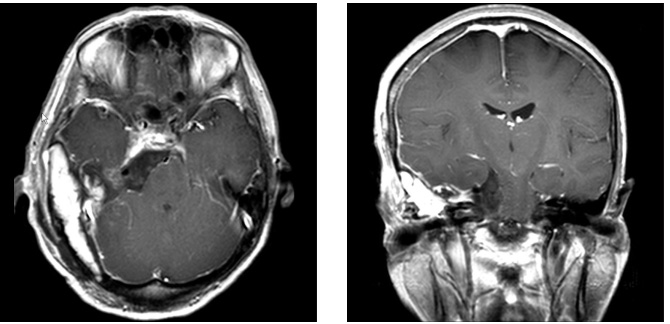

症例3

症例3は42歳女性。意識消失にて発症。CT、MRIにて内頸動脈、中大脳動脈を巻き込む大型の前床突起部起源の髄膜腫を認める。

中大脳動脈の血流が低く、血管損傷を来す可能性もあるので、浅側頭動脈-中大脳動脈バイパスをおいた後に腫瘍内より血管を掘り起こすように摘出を行った。

細い脳深部に至る血管も保護して摘出した。術後四肢麻痺等なく回復。

術前画像:内頸動脈などの血管を巻き込み狭窄する(反対側と比較)腫瘍をみとめ周囲に脳の腫れを認める。

術後画像:腫瘍はほぼ摘出され、脳梗塞等の合併症は認めない。